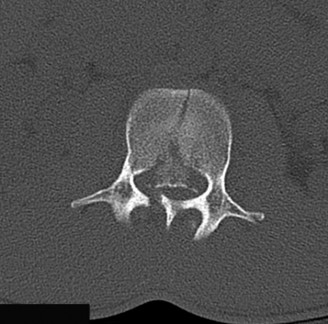

Initial trauma radiographs demonstrated a loss of anterior and middle column height at L1, with a focal kyphotic deformity. However, plain films are vastly insufficient for definitive surgical planning in thoracolumbar trauma. A high-resolution, fine-cut Computed Tomography (CT) scan of the entire spine was obtained. The CT images confirmed an L1 burst fracture with severe comminution of the vertebral body. Sagittal and axial reconstructions revealed 50% canal compromise secondary to a large retropulsed bone fragment originating from the posterosuperior aspect of the L1 vertebral body. Furthermore, the CT demonstrated 25 degrees of segmental kyphosis measured from the superior endplate of T12 to the inferior endplate of L1.

A critical finding on the axial CT slices was a vertical, split fracture propagating through the L1 lamina. This is a highly significant morphological feature. A lamina fracture in the setting of a burst fracture with retropulsion strongly correlates with a dural tear and potential entrapment of the cauda equina nerve roots. When the vertebral body bursts posteriorly, the pedicles are driven outward, and the lamina fractures as the spinal canal attempts to expand to accommodate the retropulsed bone. If the dura is lacerated, nerve roots can herniate through the dural defect and become incarcerated in the laminar fracture site.